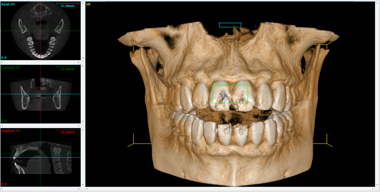

"La CBCT (Cone Beam Computed Tomography) è una tecnologia avanzata di imaging tridimensionale che permette di visualizzare con precisione ossa, denti e strutture anatomiche del cavo orale. Grazie a immagini dettagliate e accurate, consente di pianificare in sicurezza interventi chirurgici, posizionamento di impianti dentali, rigenerazione ossea e monitoraggio della guarigione post-operatoria. La CBCT migliora la diagnosi, aumenta la sicurezza dei trattamenti e assicura risultati più predicibili.